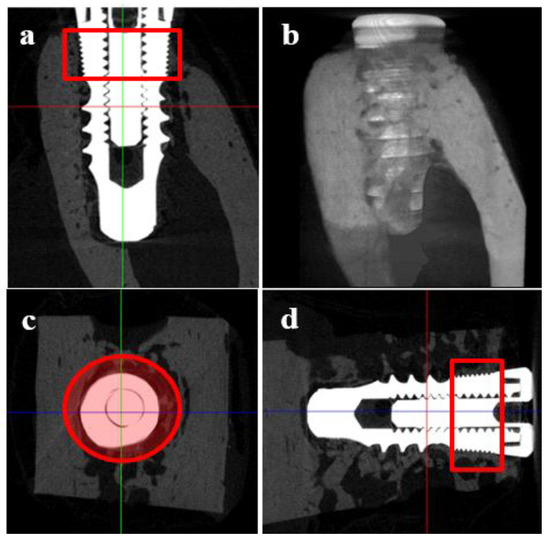

2.5.5. Micro Computed Tomography (μCT)

2.5.6. Histologic and Histometric Analysis

- Bone growth height in buccal defect areas (BG, mm): The thickness of bone that grew upward from the implant from the reference point on the buccal defect site on the alveolar ridge.

- Bone to implant contact in microthreads (microBIC, %): The bone to implant contact ratio was measured in buccal and lingual defect areas where the bone grew along the implant from the implantation reference point on the alveolar ridge.

- Bone to implant contact in macrothreads (macroBIC, %): The bone to implant contact ratio was measured in existing bone where the implant was implanted.

- Intra-thread bone density in macrothreads (ITBD, %): Intra-thread bone density was measured in the existing bone where the implant was placed.

3.4.3. Micro Computed Tomography (μCT)

3.4.4. Histomorphometric Analysis